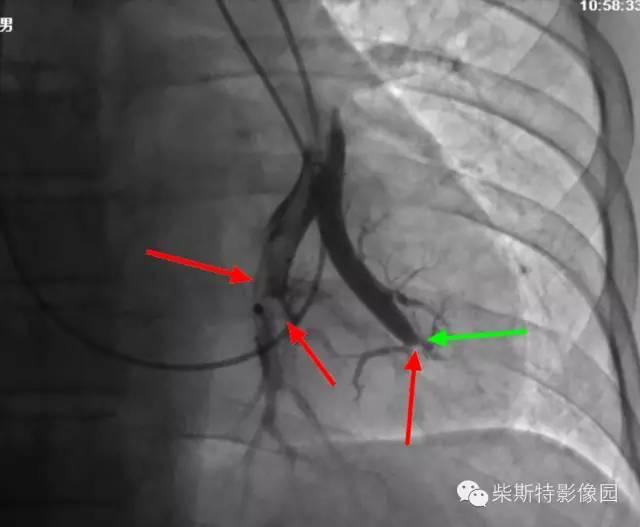

第一大名捕:肺动脉造影

红色箭头所指处即为栓子导致的充盈缺损。尽管肺动脉造影目前已经被肺动脉CTA所替代,但是其“老大”的地位还是无法撼动!

“老大”的绝招是其不仅可以提供整体的肺血管的解剖学资料,而且可以提供血流动力学参数,即可以用于诊断也可以用于治疗,如急性肺栓塞的导管内局部溶栓、捣栓、碎栓、抽栓,先天性肺动脉狭窄的球囊扩张、支架植入、肺动静脉瘘的栓塞治疗等。